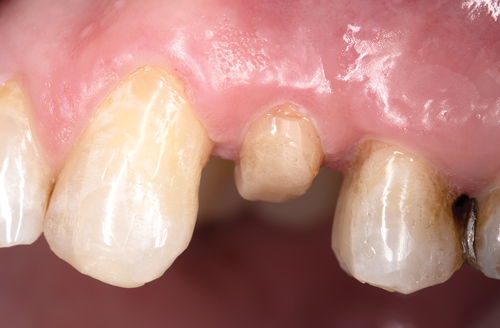

Fig 2. Restorative failure of an existing amalgam restoration on the maxillary left first premolar from recurrent caries.

Figure 2

Restorative failure of an existing amalgam restoration on the maxillary left first premolar from recurrent caries is documented here (Figure 2). The periapical radiograph revealed an extensive carious lesion extending into the pulp chamber. After clinical and radiographic evaluation, a treatment plan was discussed with the patient that included endodontic therapy, crown lengthening, and reinforcing the root and supporting the tooth-restorative complex with a fiber-reinforced post and core system.